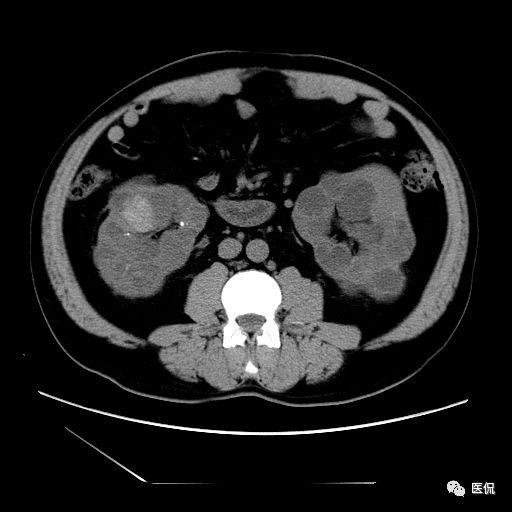

双肾实质可见多发囊性密度灶,其内密度不均匀,并可见钙化灶,增强扫描未见明显强化灶。肾周脂肪间隙清晰,与邻近组织分界清楚。

多囊肾的 CT 表现主要表现为双肾增大,轮廓光滑或有分叶,肾实质内多个大小不等的囊肿呈蜂窝状,多呈水样低密度,增强扫描囊肿本身无强化,而囊肿间正常肾组织增强,对比明显。当囊肿张力过高,使囊壁上毛细血管牵拉破裂出血时,表现为囊肿内稍高密度影,随访CT 值减低。囊壁钙化,表现为点线状高密度影像,随访CT值无变化。有文献报道约 30%病例可并发多囊肝或多囊胰。